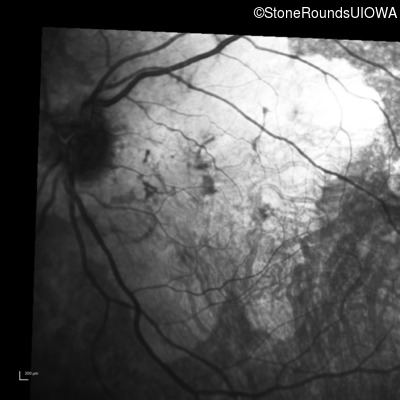

Infrared Fundus Photograph - Left - 20/200

Exemplar